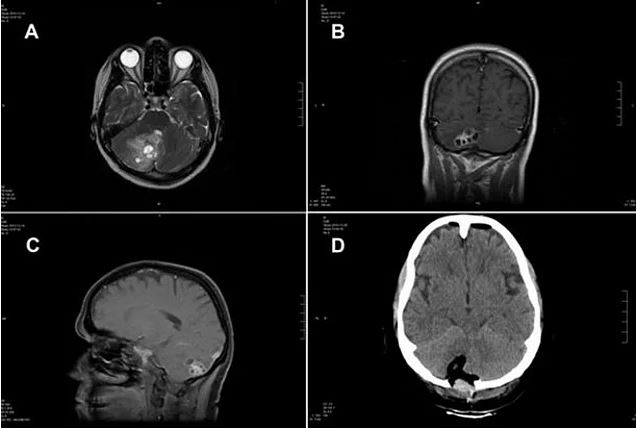

Rosemary alvarez beyninde tümör olduğunu düşünüyordu. doktora gidip ameliyata girdiğinde, doktorlar kadının beyin köküne yapışmış bir tenya olduğunu gördüler. başarılı geçen ameliyat sonrası rosemary iyileşti. tenya, zavallı kadının beynine insan dışkısı bulaşmış bir yemek yediği için yerleşmişti.